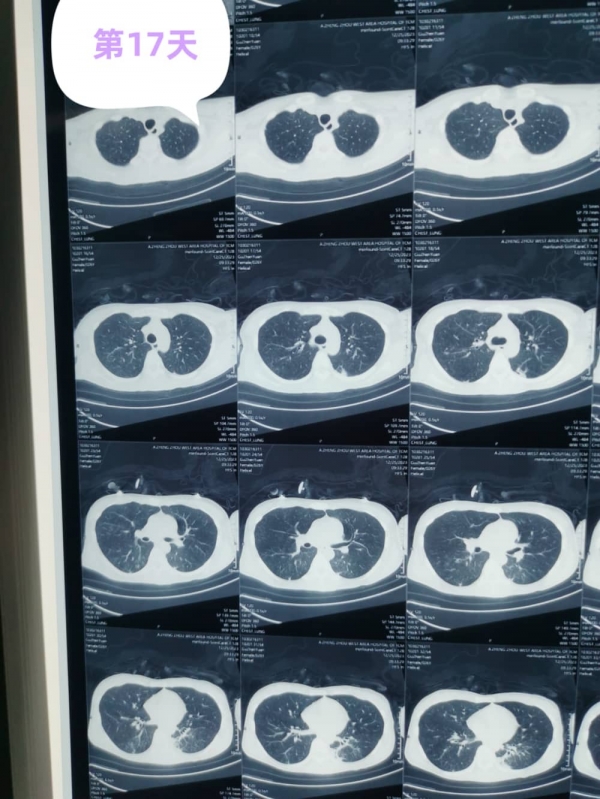

在堅(jiān)持的信念中,科學(xué)的治療下,精心的護(hù)理中,經(jīng)過17天的緊張救治,小顧的胸部CT明顯好轉(zhuǎn),生命終見曙光。